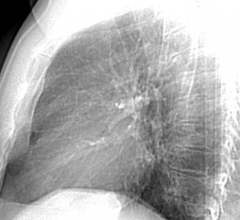

It seems a picture is worth more than a thousand words for people who see evidence of coronary artery disease, the most common type of heart disease in men and women. Simply seeing a build-up of calcium in the walls of arteries appears to prompt patients to better adhere to both statin therapy and recommendations for weight loss, according to research presented at the American College of Cardiology’s 61st Annual Scientific Session in Chicago.